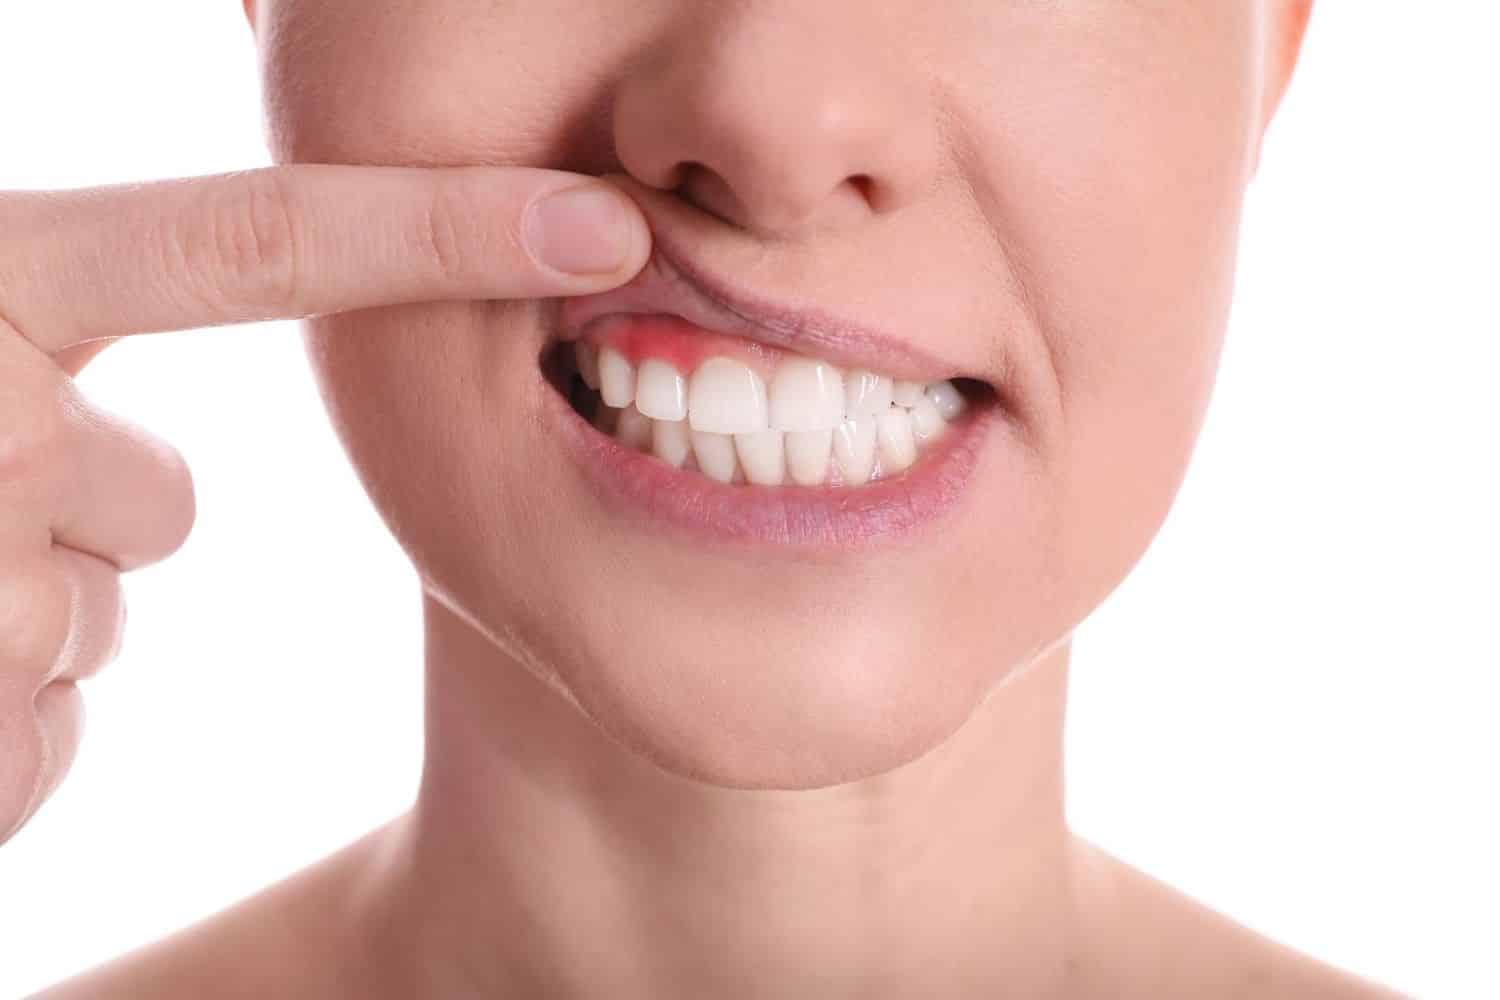

Konturimi i mishrave është i përshtatshëm për pacientët që kanë vijë mishrash të pabarabartë ose buzëqeshje ku mishrat duken më shumë se sa duhet. Procedura rregullon formën e mishrave për të krijuar përmasa më të balancuara të dhëmbëve dhe një pamje më natyrale.

Konturimi i mishrave është një procedurë estetike që rregullon vijën e mishrave. Ajo përdoret kur mishrat mbulojnë tepër dhëmbët ose janë të pabarabartë. Qëllimi është një pamje më e rregullt dhe natyrale e buzëqeshjes.

Gjatë procedurës, sasi të vogla të indit të mishrave riformësohen ose hiqen me kujdes për të zbuluar më shumë nga sipërfaqja natyrale e dhëmbit. Kjo i bën dhëmbët të duken më të gjatë, më proporcionalë dhe më simetrikë.

Gingivektomia

Heq indin e tepërt të mishrave për të zbuluar më shumë sipërfaqe të dhëmbit. Zgjidhet kur mishrat mbulojnë shumë dhëmbët.